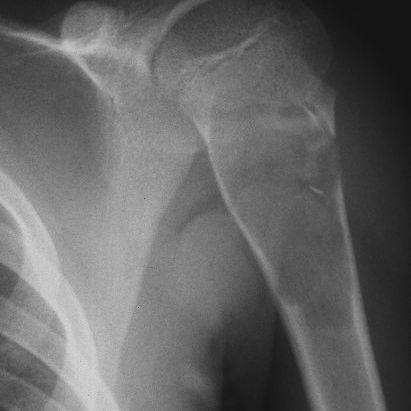

In questi casi ci troviamo di fronte a una frattura patologica su cisti ossee; anche in questi casi il reperto è occasionale dopo un trauma minimo accidentale. Possono riscontrarsi in varie parti del corpo, normalmente a carico delle ossa lunghe quali omero ( immagine a lato)  oppure in sede peroneale ( caso in basso ).